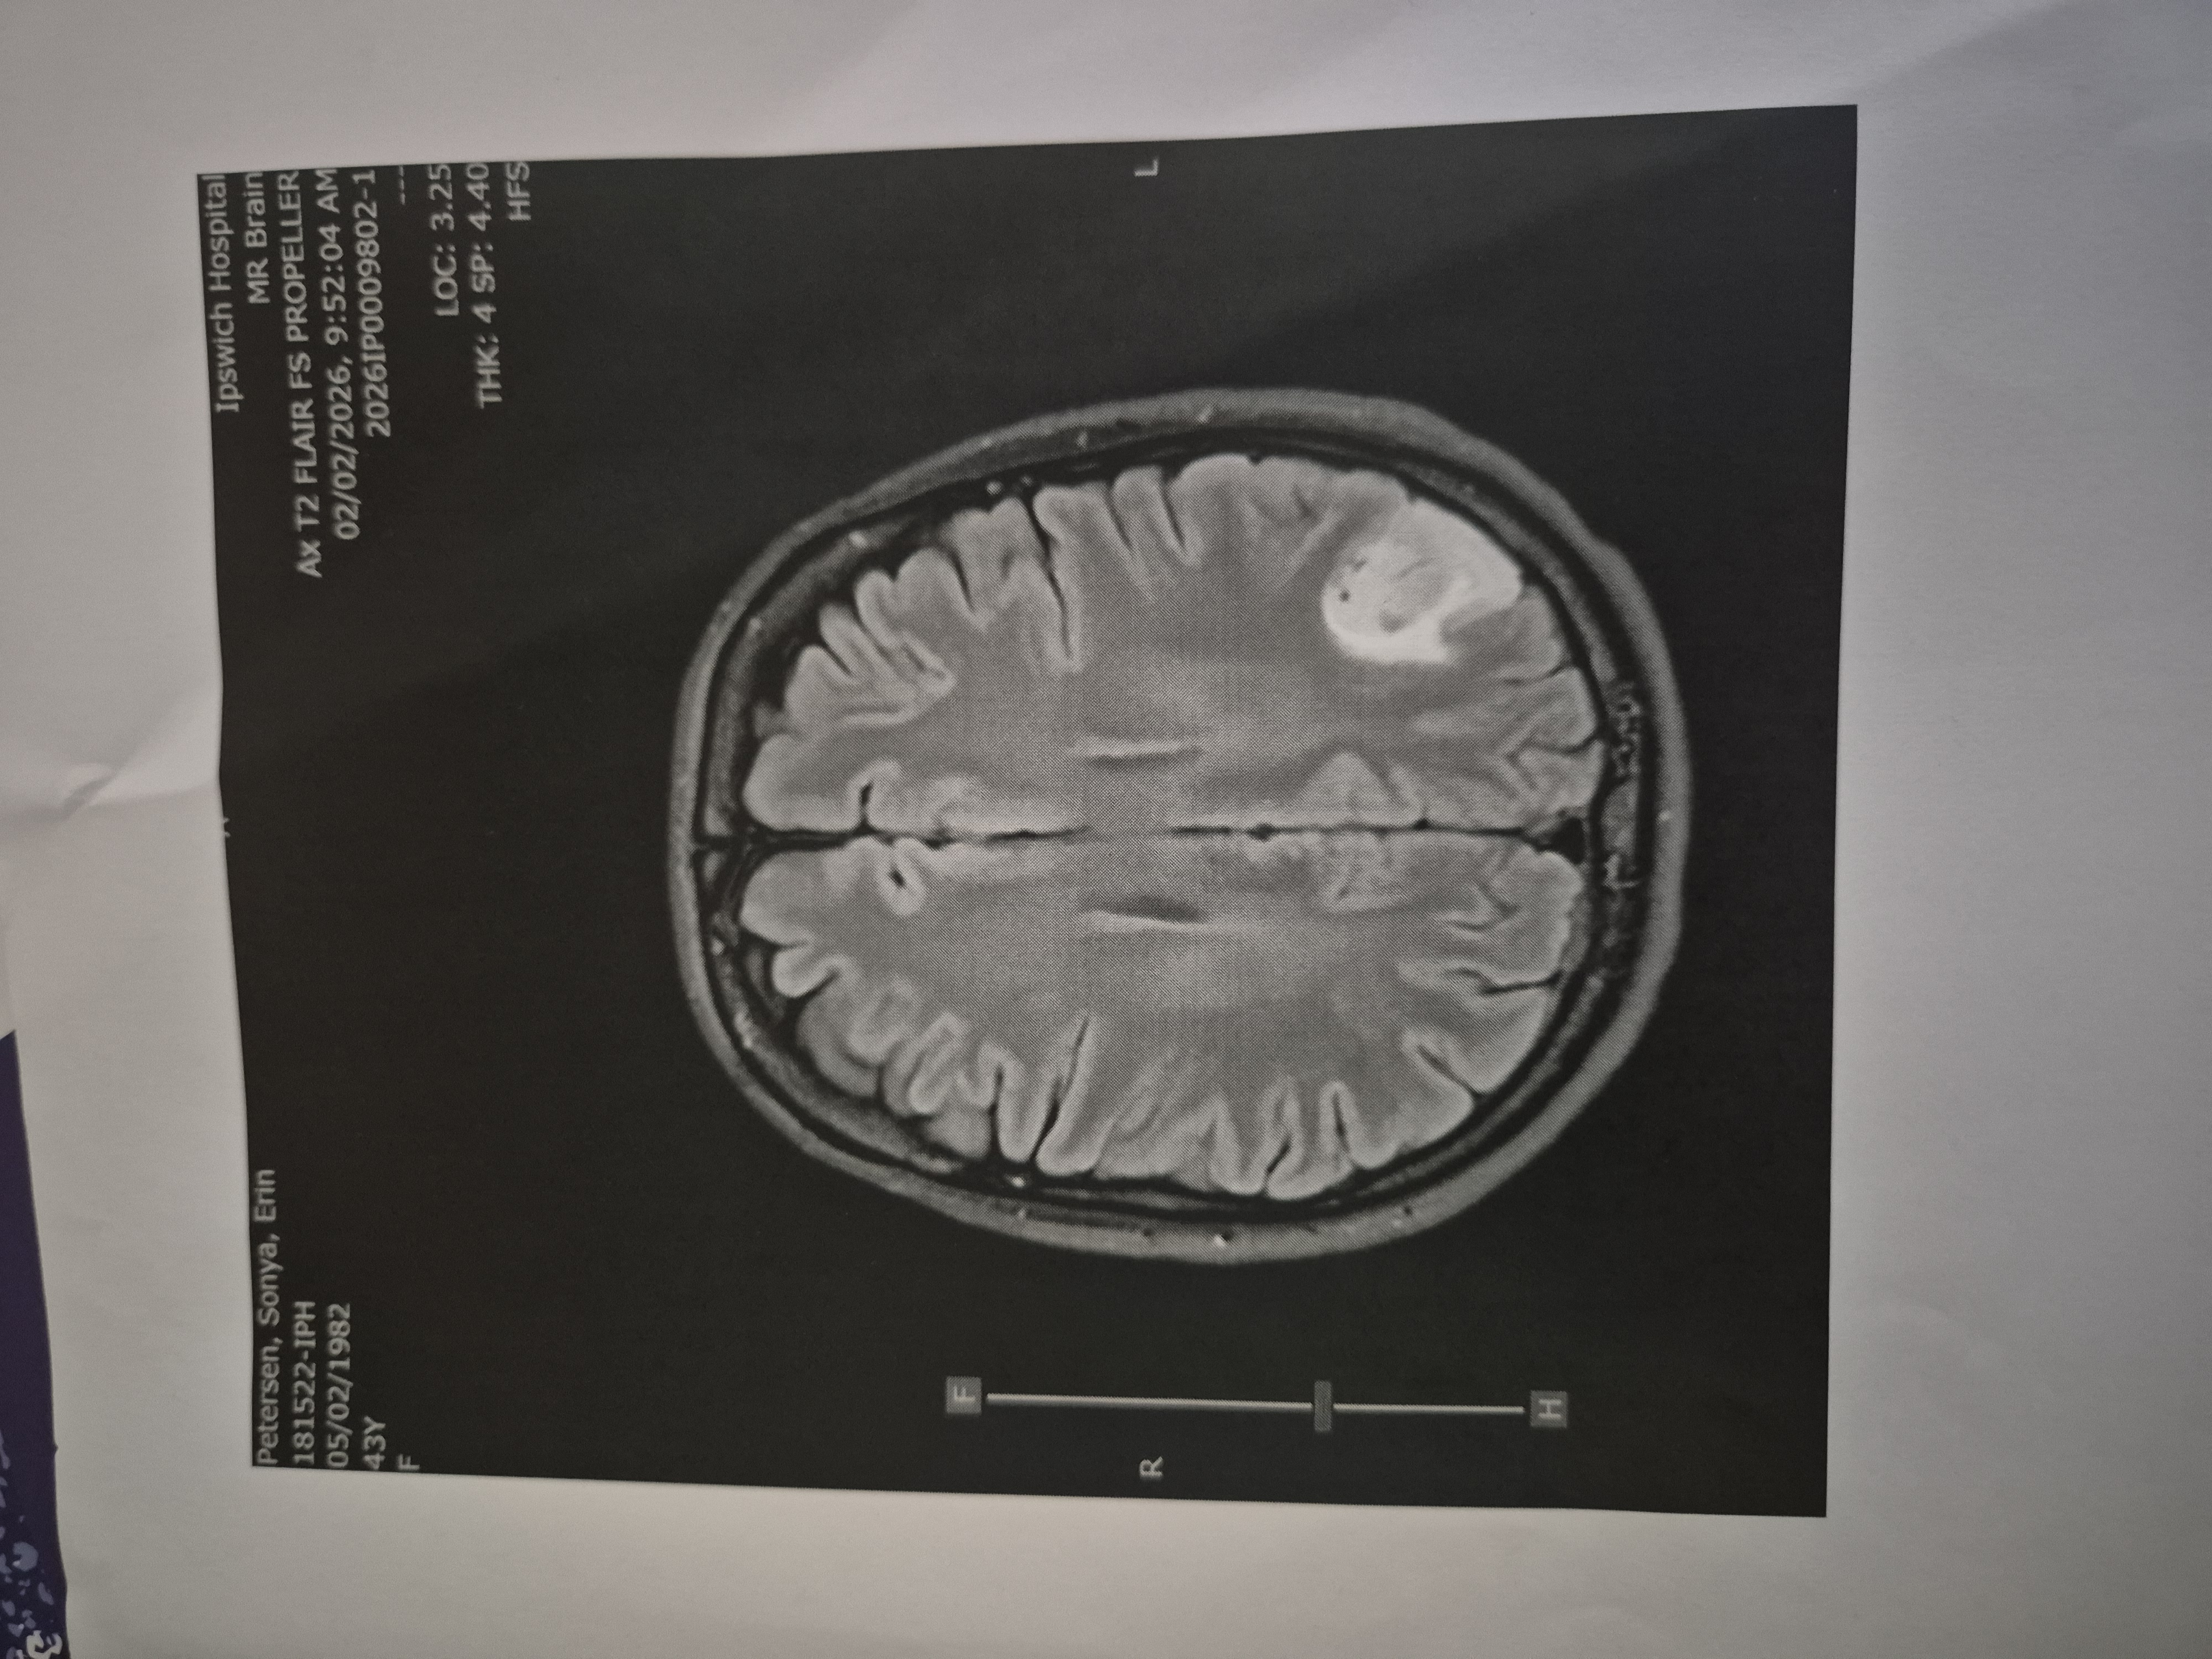

Anyway. . . I have a brain tumor. TaDaaah . . .